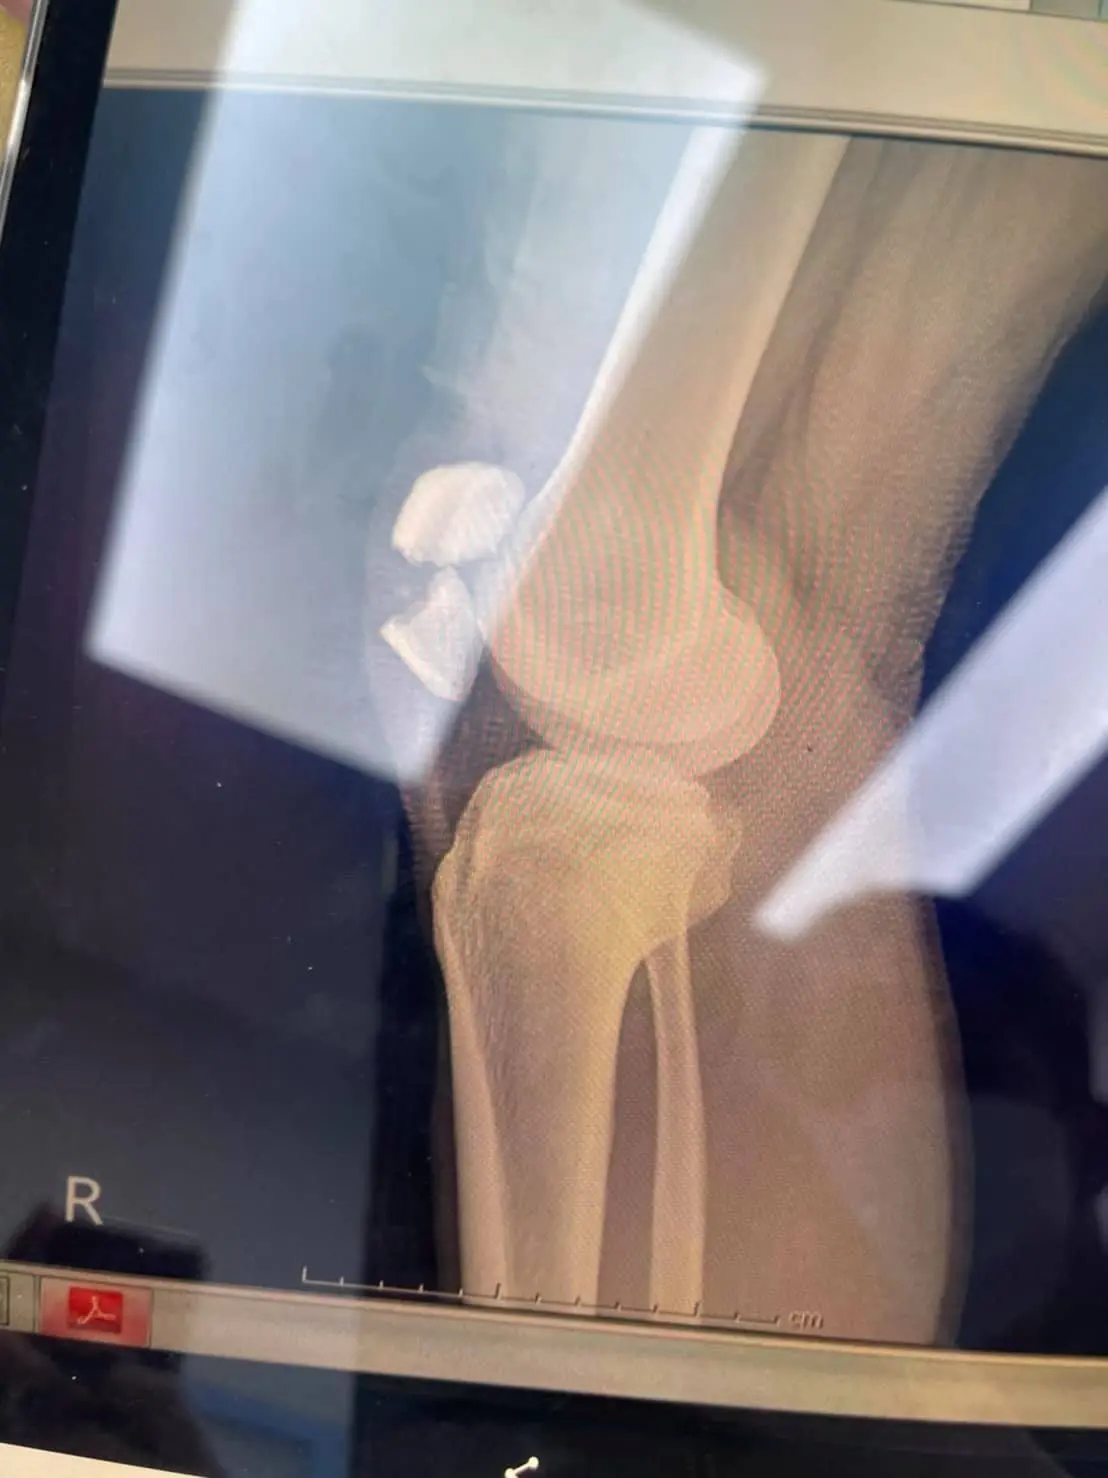

Part1 ณ ที่เกิดเหตุ คนเจ็บเคยเล่นทั้งสเก็ตและเซิร์ฟ ปกติก็ล้มประปรายเวลาแสนป เลยให้ใส่เซฟตี้ แต่ก็ใส่ๆถอดๆ (ผช. ชอบคิดว่าดูอ่อนและไม่เท่ห์ รอบหน้าอยากเท่ห์จะสั่งชุดไอรอนแมนให้ใส่แม่ม!!) ตอนล้มไม่ได้เร็วมากแต่เป็นช่วงกะลังโค้ง นางบิดตัวละบอร์ดพลิก อนิจจัง อนิจจา บอร์ดตั้ง ละล้มหน้าคว่ำหัวเข่าป้าบเข้าให้กับสันอย่างแรง (หมอถามเลยดูจากงานแล้วเหมือนโดนรถชนกระแทกอย่างแรงเลยนะล้มเฉยๆยังงัยก็ไม่ขนาดนี้) อ่ะกลับมาที่เกิดเหตุ เมื่อทุกคนเห็นเข่าเลยไม่ให้ขยับนอนนิ่งไว้ก่อนรอจนรถมูลนิธิมา เค้าตรวจเช็คเบื้องต้นบอกว่าน่าจะแค่หลุดเพราะคนเจ็บไม่ปวดมาก เลยเคใจชื้นนิดนึง

Part3 รพ. ที่รักษาตัวย้ายมาเรียบร้อยรอคุยกับหมอคุยเรื่องคชจ. คร่าวๆ (พนง. แจ้งว่าเบาๆรวมทุกอย่างไม่เกิน 360,000 แน่นอนค่าาา จ้าราคาน่ารัก) เหตุการณ์เกิดห้าทุ่ม ได้ขึ้นห้องตีสี่กว่า ตลอดระยะเวลาคือยังไม่ได้ทำอะไรกับส่วนที่แตกนะคะ จริงๆหมอแจ้งว่า ก็ไม่ถึงกับเป็นเคสผ่าฉุกเฉินรอได้ แค่จะขยับละเจ็บมาก ถ้าได้ผ่าก็จะเจ็บที่แผลแทน ก็เท่ากับว่านอนเล่นรพ. หนึ่งคืนรอหมอมาคุยสิบโมง สรุปคือไม่ได้เปลี่ยนสะบ้า แต่จะใช้น็อตสองตัวยืด และเข้าเฝือกช่วงเข่าไว้แค่นั้น จะได้ผ่าหกโมงเย็นใช้เวลาประมาณชม. ครึ่ง หลังจากนั้นถ้าไม่มีภาวะแทรกซ้อน และฟื้นตัวเร็วสามวันก็อาจกลับได้ แต่ขาก็จะต้องเหยียดตรงอย่างนั้นไปสักระยะ หลังจากนั้นก็ทำกายภาพเอา ต้องคอยขยับให้เลือดหมุนเวียน ใช้เวลาฟื้นตัว3-6 เดือน แต่ส่วนนั้นก็คงไม่ได้ดีเหมือนเดิมร้อยเปอร์เซ็นต์ (แต่ไม่ขาเป๋น้า)